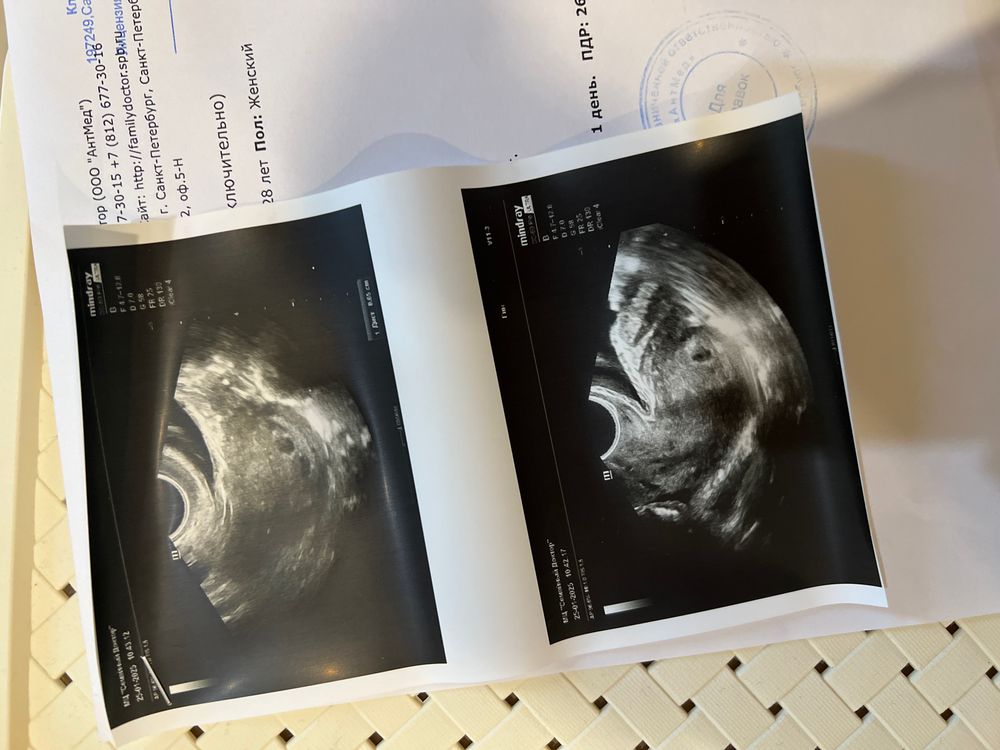

плодное яйцо видно, а вот желточный мешок не визуализируется и эмбрион.

Когда хгч около 1000, то можно увидеть плодное яйцо (пя). А желточный мешочек - когда хгч около 20 тыс при пя не менее 10 мм , а эмбрион - хгч около 30 тыс при пя 16 мм, сердцебиение - еще позже.

У Вас срок очень маленький. Все верно Вам сказали, приходите через 2 недели в 7 недель и будет видно эмбрион и даже сердцебиение

У меня на сроке 6недель и 5 дней было плодное яйцо 19мм, желточного мешка и эмбриона не нашли. Через неделю сердечко уже стучало. Желаю вам удачи!

Все хорошо, у меня при ПЯ 6 мм тоже не увидели ЖМ и эмбрион, через 2 недели уже с сердцебиением все было)) не волнуйтесь !